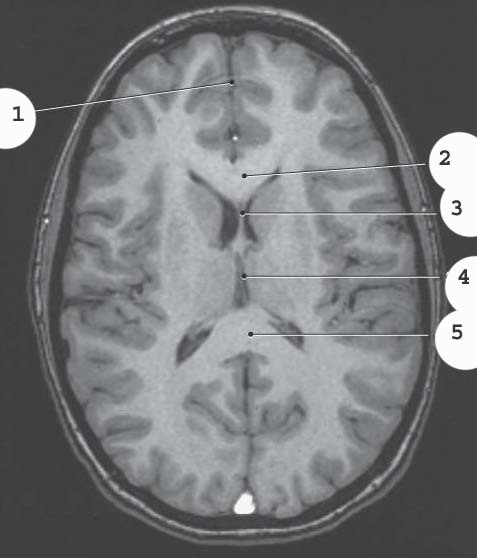

1

White matter

2

gray matter

4

lateral ventricle

5

suprasellar cistern

6

Longitudinal fissure

7

sphenoid sinus

Superior Sagittal sinus